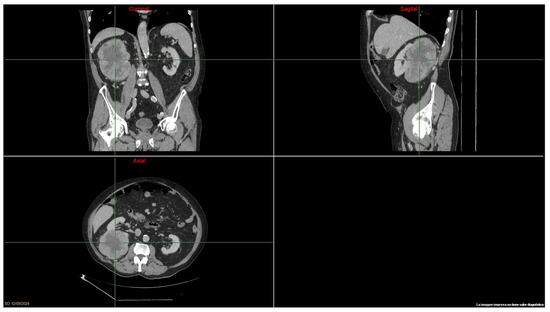

Figure 1

Show Figures